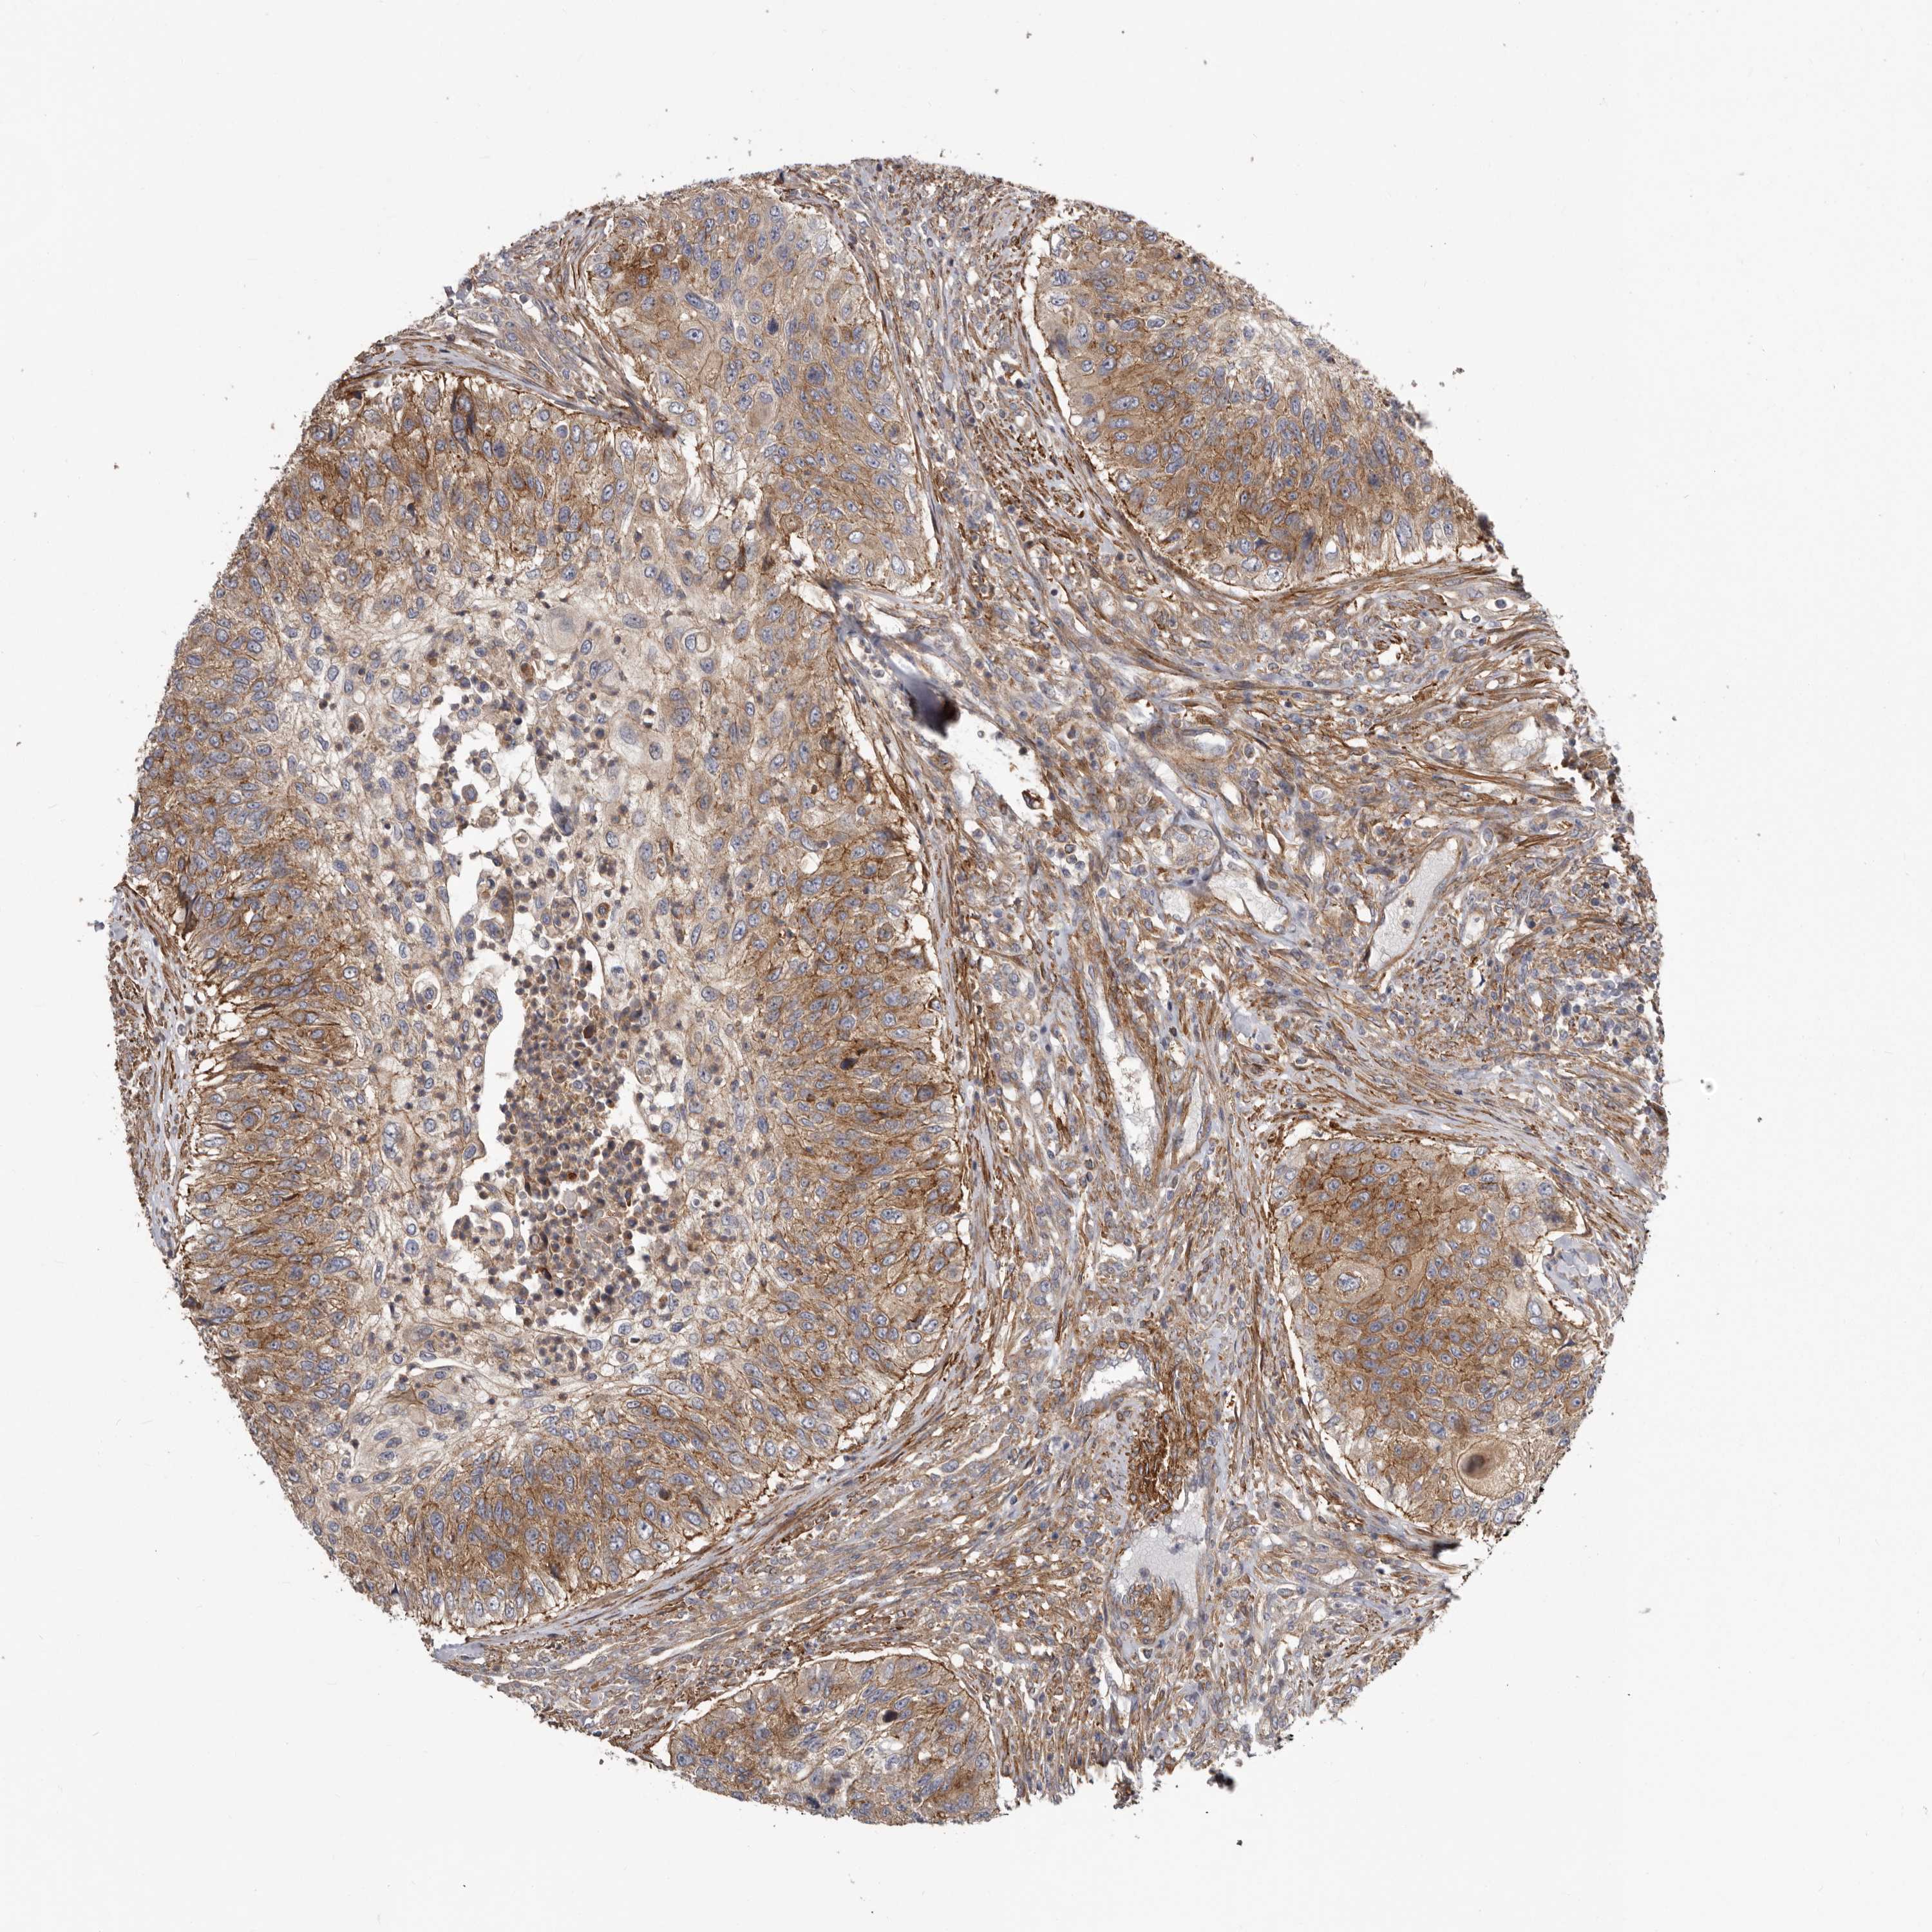

UROTHELIAL CANCER - Protein expressioni

A mouse-over function shows sample information and annotation data. Click on an image to view it in a full screen mode. Samples can be filtered based on level of antibody staining by selecting one or several of the following categories: high, medium, low and not detected. The assay and annotation is described here.

Note that samples used for immunohistochemistry by the Human Protein Atlas do not correspond to samples in the TCGA dataset.

Antibody stainingi

Antibody staining in the annotated cell types in the current human tissue is reported as not detected, low, medium, or high, based on conventional immunohistochemistry profiling in selected tissues. This score is based on the combination of the staining intensity and fraction of stained cells.

Each image is clickable and will lead to virtual microscopy that enables deeper exploration of all samples and also displays staining intensity scores, fraction scores and subcellular localization as well as patient and tissue information for each sample.

Antibody HPA028448

Antibody HPA028696

Urothelial carcinoma, Low grade

Urothelial carcinoma, High grade